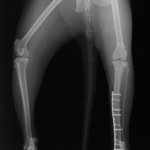

ペルシャ猫 11ヶ月齢 雄

他院にて左大腿骨遠位の成長板骨折(salter-harrisⅠ型)が認められており、治療相談を目的として来院。当院にて、キルシュナーワイヤーを用いたピンニングにより骨折部位の整復を行いました。術後の経過は良好で、現在も経過観察中です。

術後レントゲン

Arthrex社のターゲティングデバイスを用いてピンニングの位置を調整することで、確実な固定を行っています。当院ではこの手術器具以外にも、人の手術にも使用される様々な器具を導入し、手術精度を高め、また医療メーカーと新しい器具の開発、試作にも取り組んでおります。